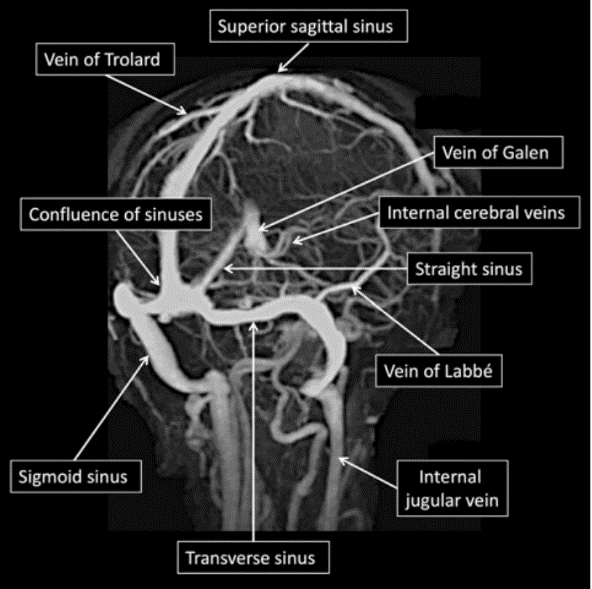

图-7脑的深静脉模式图大脑内静脉( internal cerebral veins)左,右各

8大脑内静脉内侧面观大脑大静脉( great cerebral vein)又称galen静脉

基底静脉和一条大脑大静脉( galen 静脉) , 每侧大脑内静脉由透明隔

1,大脑大静脉大脑大静脉(great cerebral vein)又称galen大静脉(great

脑中静脉与罗森塔尔基底静脉汇合形成galen静脉皮质浅静脉trolard- 最

galen大脑大静脉接受枕内侧静脉,后胼周静脉,上蚓静脉,小脑前中央静脉